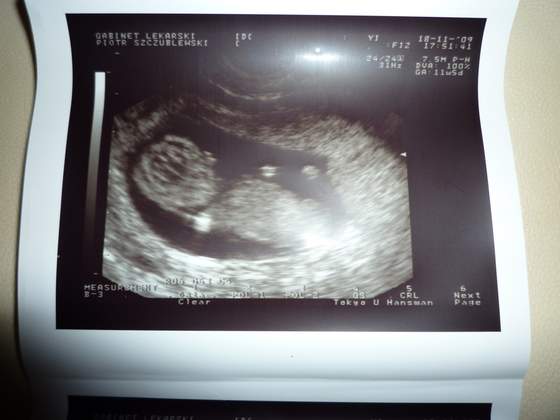

Nasze fasolki na USG

a o to moje dzieciątko, cały czas się wiercił i ciężko było pstryknąć :)

18-11 , 12 t i 3 d